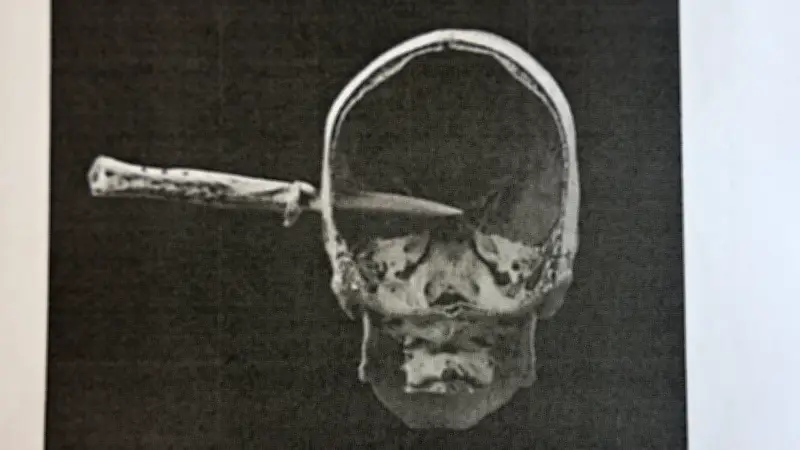

Vor einem Plattenbau in der Oberlausitz kam es zu einer tragischen Gewalttat, die einen 30-jährigen Mann das Leben kostete. Der Täter, der nun vor Gericht steht, griff mit einem Springmesser an und traf sein Opfer am Kopf. Die Attacke, die laut Ermittlungen aus Eifersucht erfolgte, endete tödlich für den jungen Mann.

Die Messerattacke erfolgte plötzlich und ohne Vorwarnung, was die Tragödie noch erschütternder macht. Der Einsatz eines Springmessers als Tatwaffe unterstreicht die Brutalität des Vorfalls. Die Ermittler arbeiten daran, alle Details aufzuklären, um Gerechtigkeit für das Opfer und seine Angehörigen zu gewährleisten.